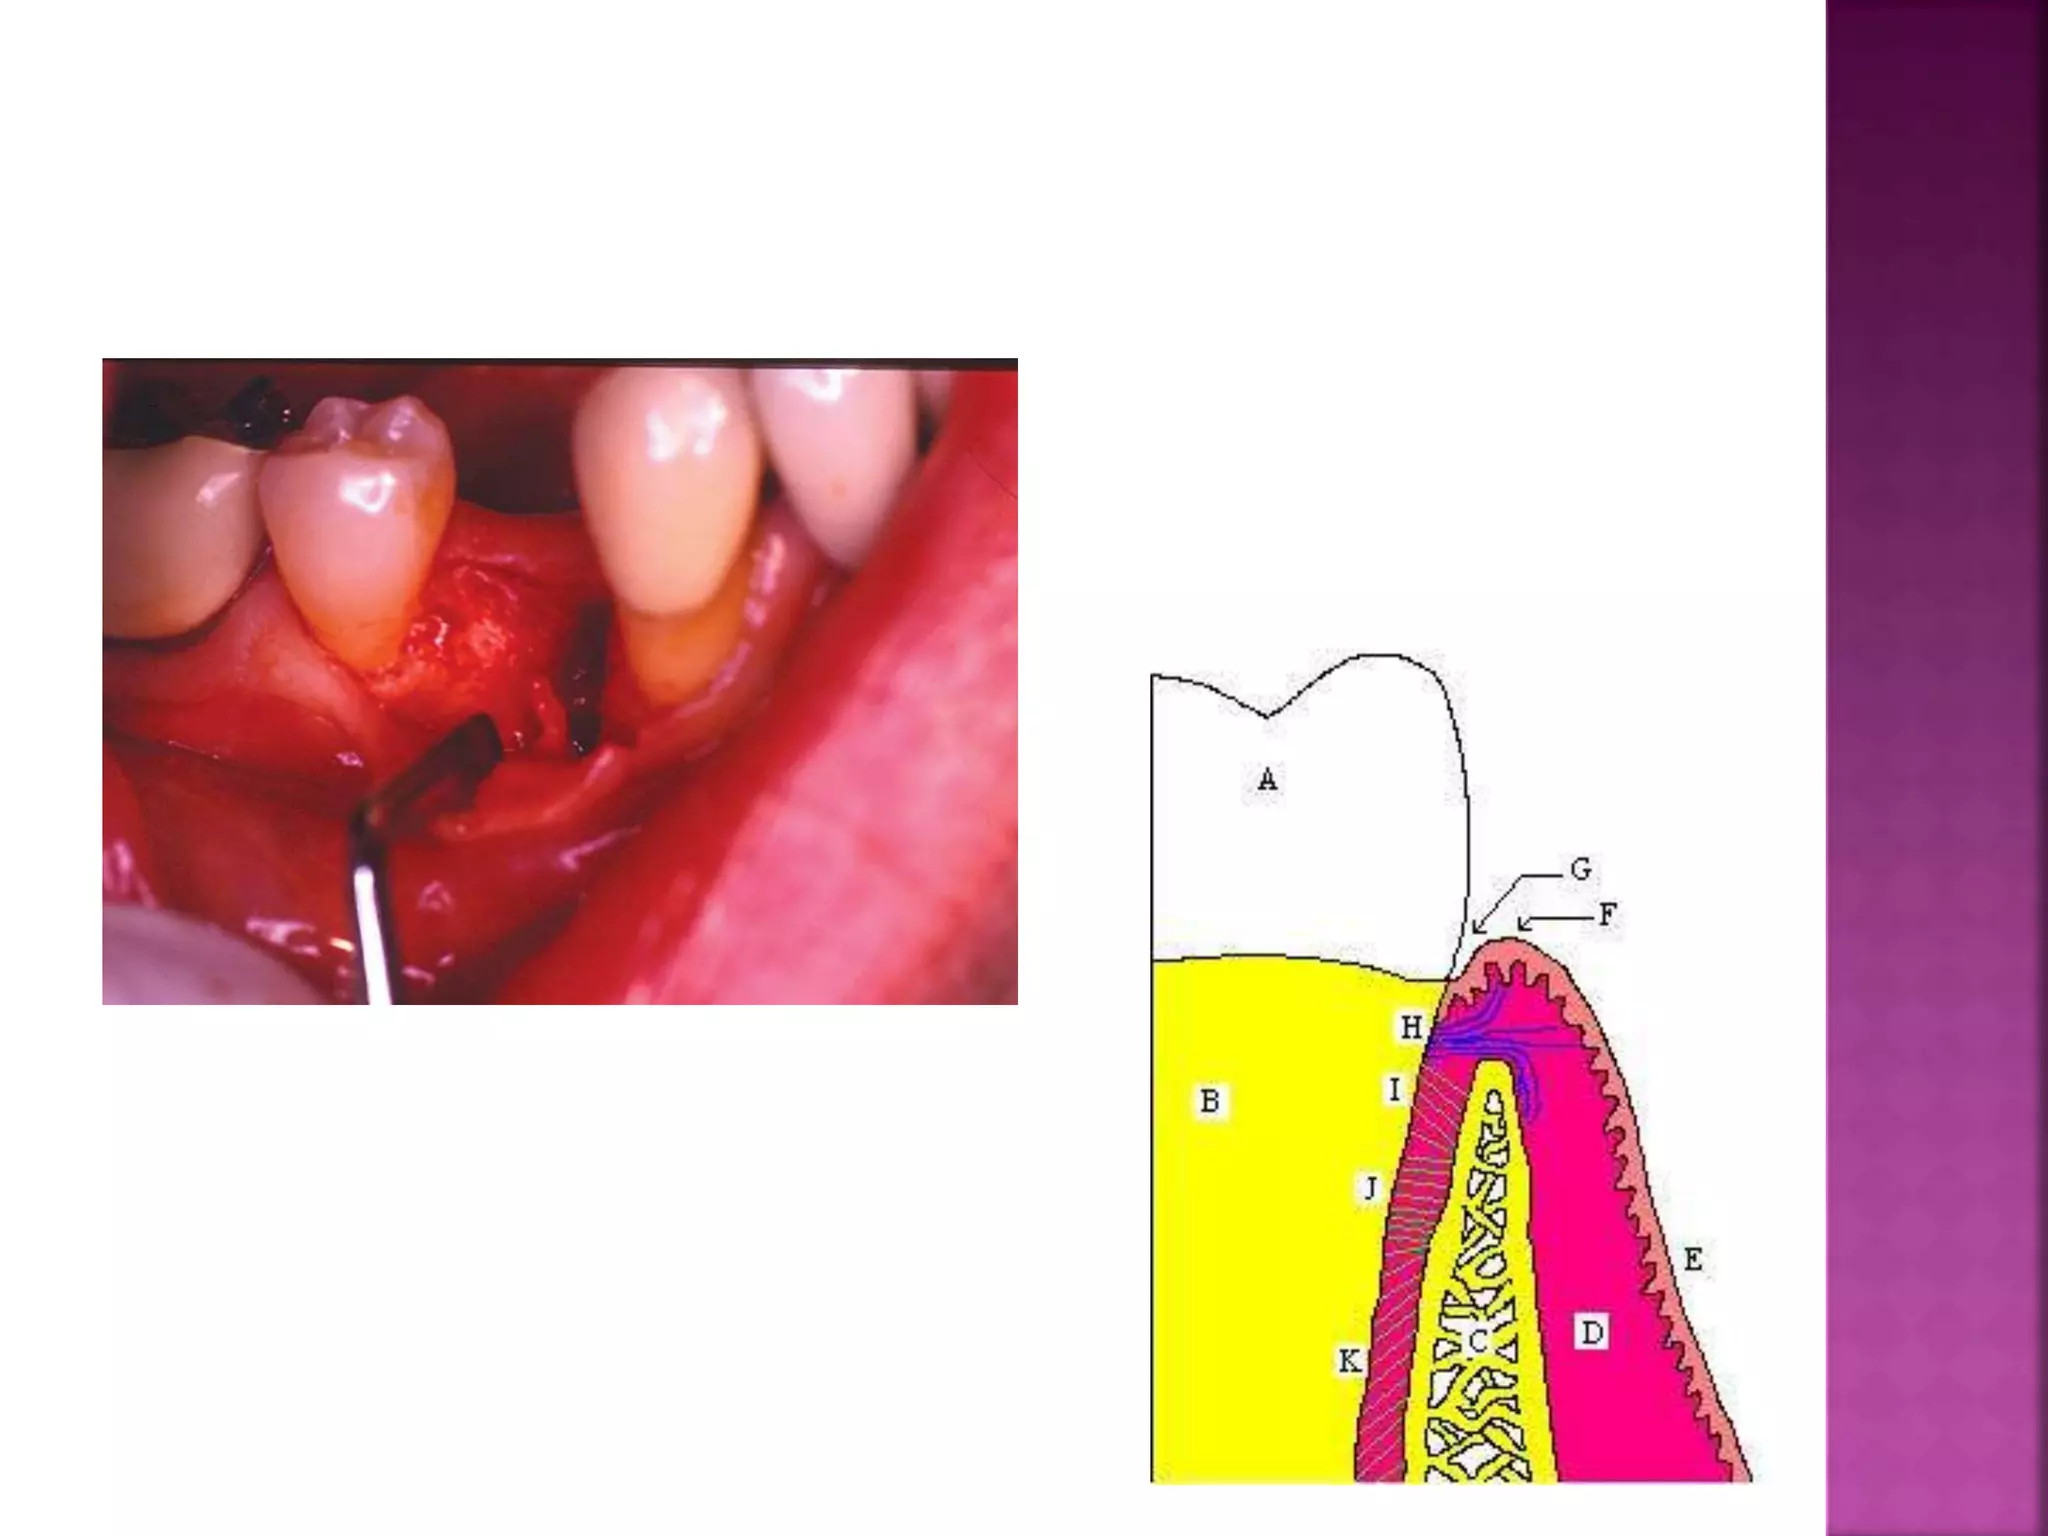

III - APPROXiMAL CONTACT :

There is a continuous growth

of bone at the fundus of

the sockets of teeth and at

the crests of the alveolar

processes .

This growth is rapid in

young persons , slows

down in the thirties but in

the healthy dentition it

never ceases entirely.

 There is also

constant growth of

bone on the distal

wall of each socket,

whereas the mesial

wall shows

resorption of bone

alternating with

localized reparative

apposition .

The roots of the teeth also

enlarge and this enlargement

does not cease when the root

is fully formed. By continuous

apposition of cementum the

roots grow slightly in its

transverse diameters and more

rapidly in length.

 Elongation of the

root and growth of

bone at the

fundus, of the

socket are

correlated with a

continued vertical

eruption of the

tooth during its

functional period.

The changes on the mesial and distal alveolar walls are

correlated to a movement of all teeth toward the

midline, i.e., mesial drift .